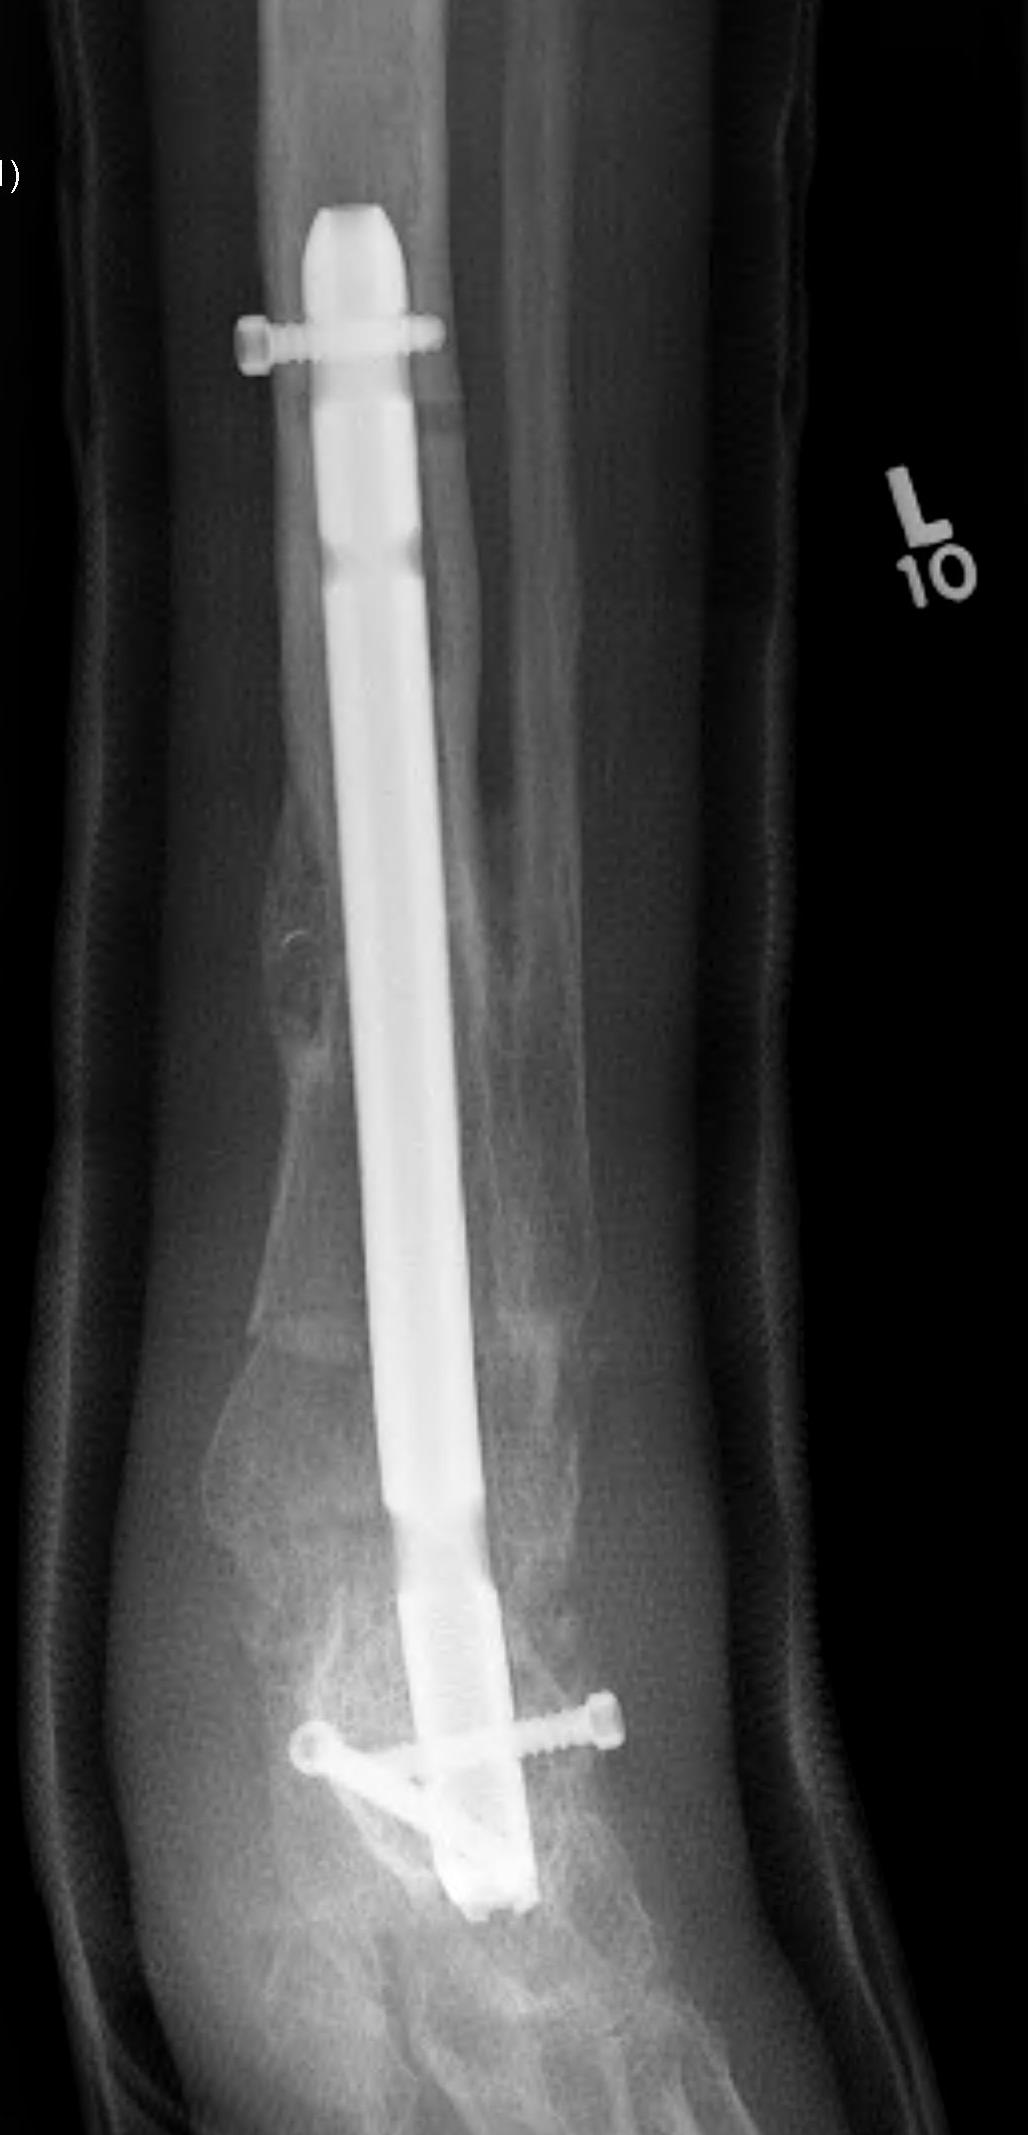

Tibiotalocalcaneal (TTC) / hindfoot nail

Insertion point

- in line with 2nd metatarsal / center of heel pad

- junction of posterior 2/3 and anterior 1/3 heel

- should pass through anterior aspect posterior subtalar joint

- posterior to lateral plantar artery and nerve

Screw fixation

- distal screw fixation in calcaneum +/- talus with jig

- compression

- proximal screws medial to lateral